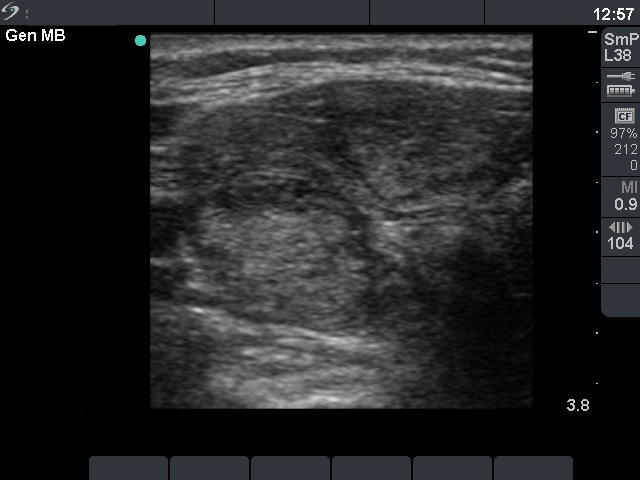

Ultrasonography: the thyroid was hypoechogenic with two well-circumscribed hyperechogenic areas in the right lobe. These were surrounded with a halo and presented perinodular blood flow.